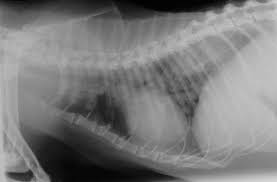

Liver Cancer In Cats Causes Symptoms Treatment All About Cats from allaboutcats.com Increased respiratory rate (>40 breaths per minute) increased respiratory effort (working harder to take breaths) The doctor will then order additional testing to rule out or confirm a cancer diagnosis. My cat had a lung xray which showed a lot of calcification my cat had a lung xray which showed a lot of calcification in her lungs. Depending on the type of cancer a cat has, you might see vomiting, diarrhea, changes in appetite and weight loss. Doc said it's definitely lung cancer, without using those words. In my experience, most cats with cancer in the lungs do not do much coughing. If you don't weigh your cat regularly at. Straining to urinate or defecate.

They are more often the result of old infections, scar. For some people with occupational asbestos exposure and other risk factors, annual ct scans may be a. Vomiting and diarrhea are common signs of gastrointestinal lymphoma. Fluid accumulation around the lungs (called pleural effusion) is common in cats with primary lung tumors. Cats present with lameness, swelling of the toes and pain The doctor will then order additional testing to rule out or confirm a cancer diagnosis. Straining to urinate or defecate. Anorexia, or loss of appetite Panting, abdominal effort when breathing, wheezing, coughing, and inability to exercise are also signs of lung tumours in cats. Cats are tricky because they hide disease well. Different cancers have different symptoms. The cat will have a dry cough and will be less active. Less than a third of cats diagnosed with lung cancer have breathing problems.

Secondhand Smoke Can Also Cause Cancer In Pets Studies Show from www.tampabay.com Cats present with lameness, swelling of the toes and pain Primary lung cancer originates in the lungs, while secondary lung cancer spreads to the lungs from some other part of the body. If your cat's litter box habits change, it may be a sign. They are more often the result of old infections, scar. Combining pet/ct technology enables our doctors to know where the healthy lung tissue ends and the tumor begins. Bad breath may indicate oral cancer, although it's also a symptom of a sinus infection. For example, certain breathing problems and coughing are surprisingly uncommon; A ct scan can detect potential cancer in a lung.

Lung Cancer Squamous Cell Carcinoma In Cats Symptoms Causes Diagnosis Treatment Recovery Management Cost from images.wagwalkingweb.com Because many cats and dogs may not show obvious signs of cancer pain and also tend to hide pain as a protective mechanism, identifying the degree of pain and the amount of suffering can be very difficult. I lost 3 kids in 9 months several years ago. In the case of lung cancer, this scan provides a more comprehensive view of the chest area to determine the presence of abnormal activity, even before a tumor may have developed. If your cat's litter box habits change, it may be a sign. Adenocarcinoma is a malignant neoplasm, making up about 75 percent of all primary lung tumors in cats. A lung nodule (or mass) is a small abnormal area that is sometimes found during a ct scan of the chest. The stage and the grade. But, there are other possibilities.